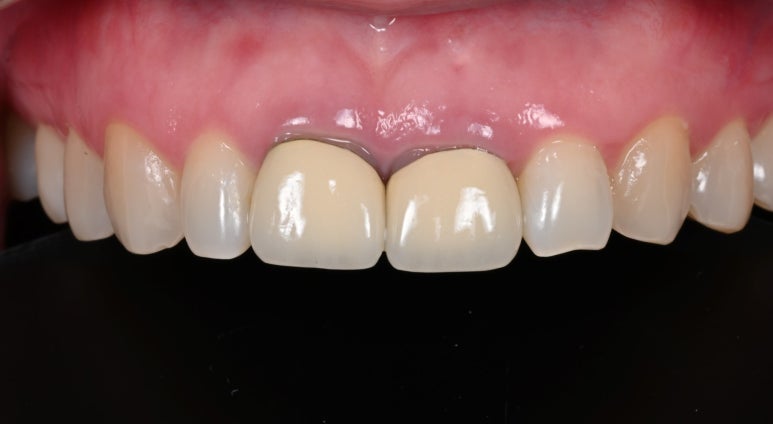

3. 임시치아 장착 & 잇몸 적응 확인

기존 크라운을 제거한 날, 치아를 다듬고 기공소에서 제작한 임시치아를 장착합니다.

그리고 신경치료를 진행하는 동안 중간중간 잇몸이 새로운 크라운 형태에 잘 적응하는지 체크했습니다.

약 3주의 기간 동안 크라운 주변 잇몸이 잘 적응한 것을 확인 할 수 있었습니다.

25.08.11 임시치아 장착

25.09.04 임시치아 장착 약 3주 후